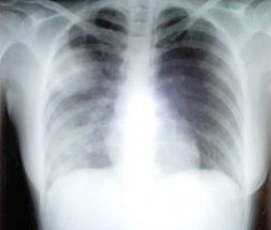

SARS患者患病十天的胸透照片